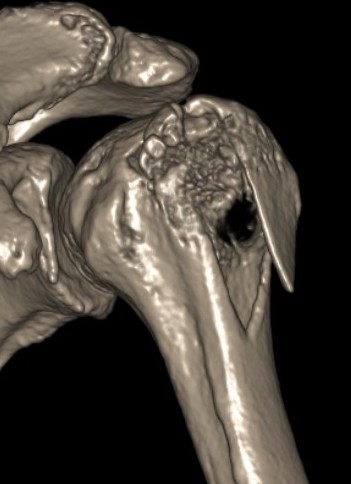

Four part

Avascular necrosis (AVN)

In most fractures, arcuate artery is disrupted, but head survives

- posterior circumflex artery is sufficient

- risk increases with amount of displacement

- 4 part fracture 30%